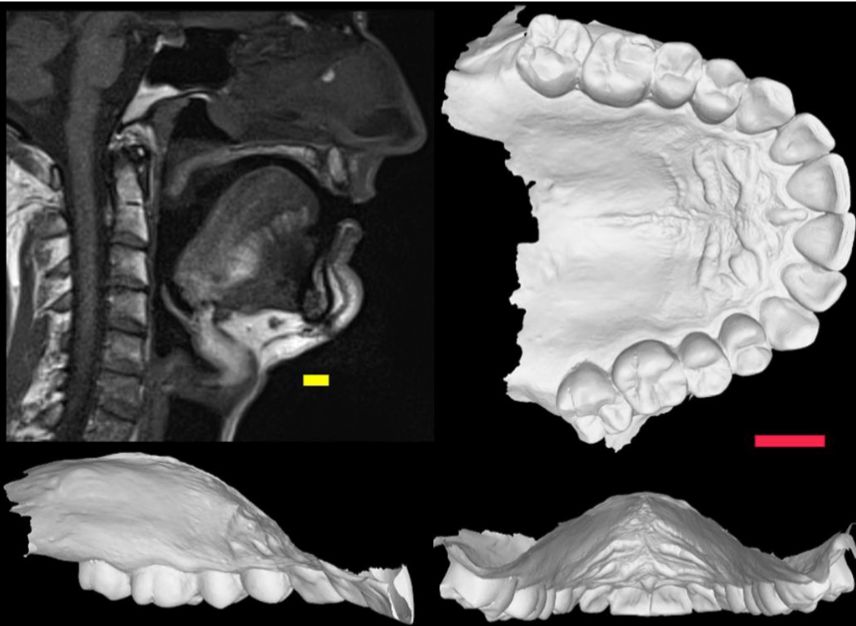

为了进一步探究发音器官结构对发音的影响,研究团队利用计算机建模模拟声道。在模型中,他们可以精确控制声道的解剖结构,并观察它对语音产生的实际影响。论文集中讨论了口腔声道的一个组成部分——硬腭,尤其是中矢状硬腭形状(midsagittal hard palate shape,MSHPS,如下图)的差异对发音的影响。

中矢状硬腭形状(MSHPS)扫描图